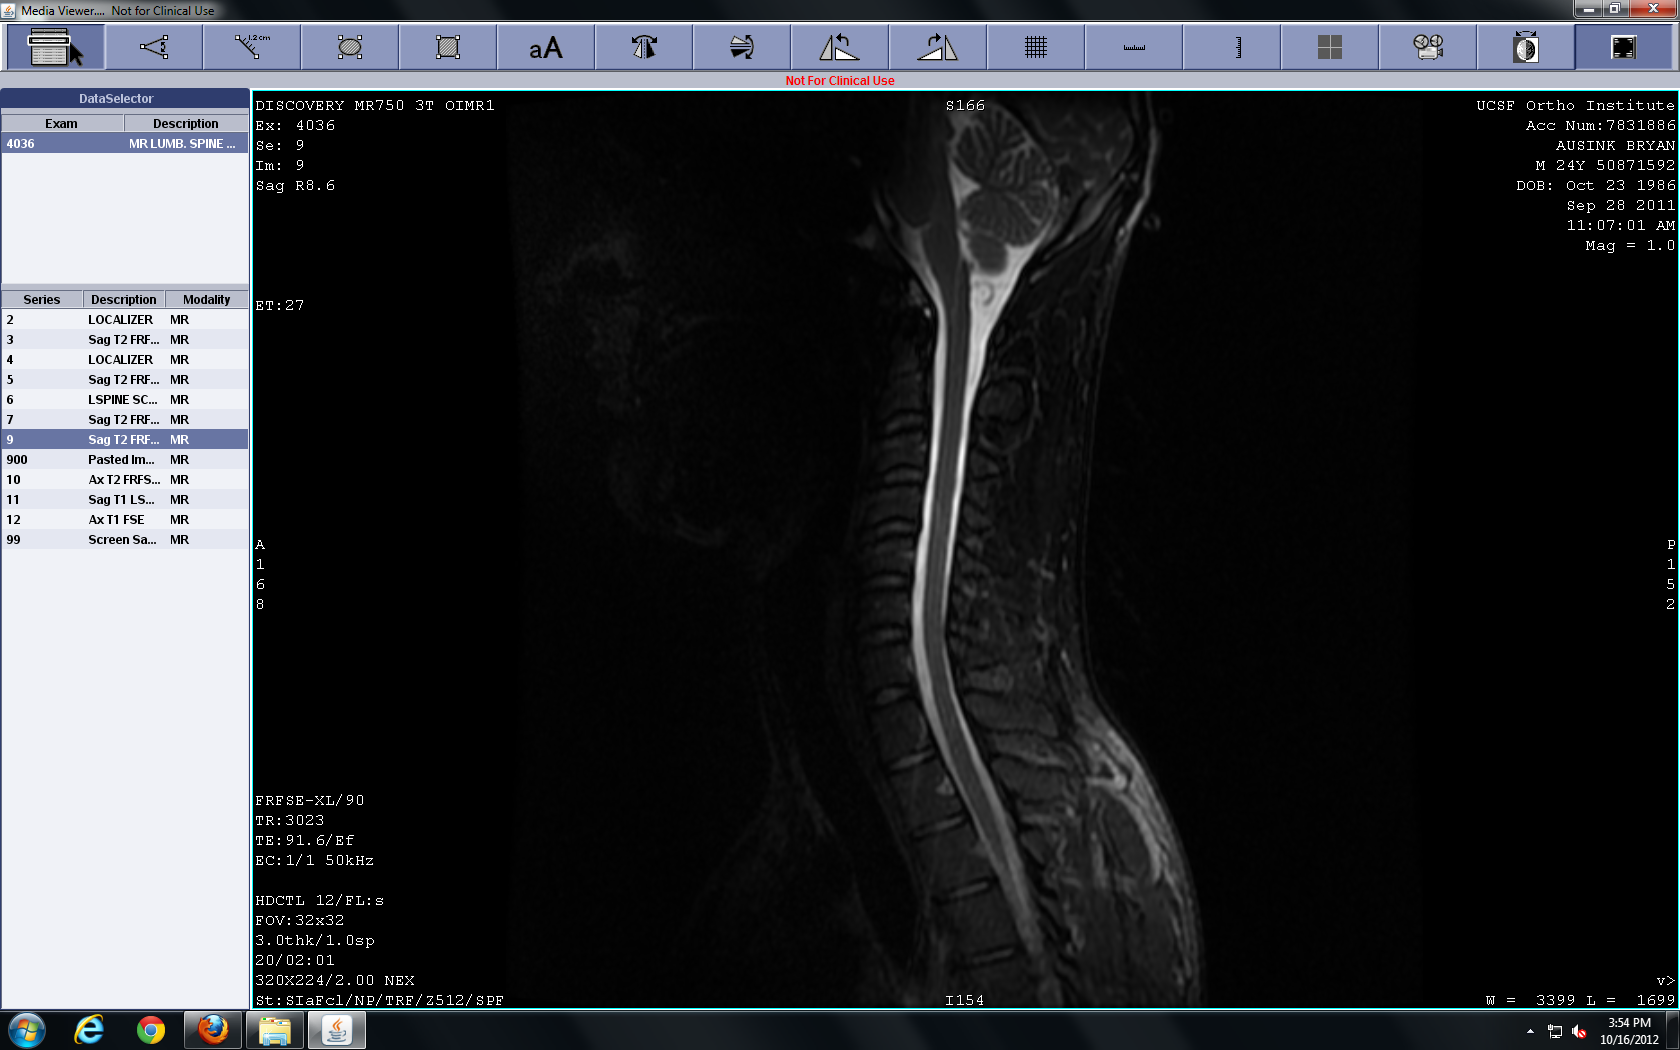

Here is an MRI of my cervical spine from 2010. I am lying down on my back and doing a chin tuck. I was surprised to find that my spine was actually straight. I can’t say that a straight spine is better than one with a smooth curve but it does show that I am not stuck in a curved position.